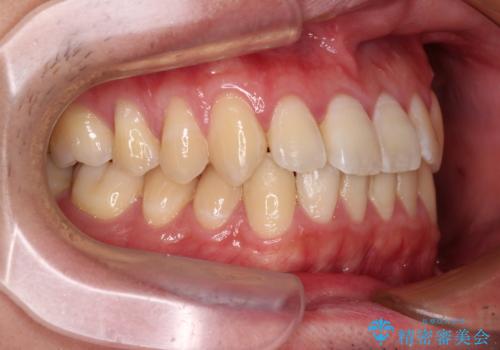

- 上下前歯のデコボコを気にして来院された患者様です。

叢生は軽微であり、費用を抑えて期間もあまりかけずに治療をしたいとのことで、インビザライン・ライトを用いて矯正治療を行うこととしました。

途中通院できなくなり、マウスピースの装着もしっかりとできなかったため、治療期間が長くかかってしまいました。